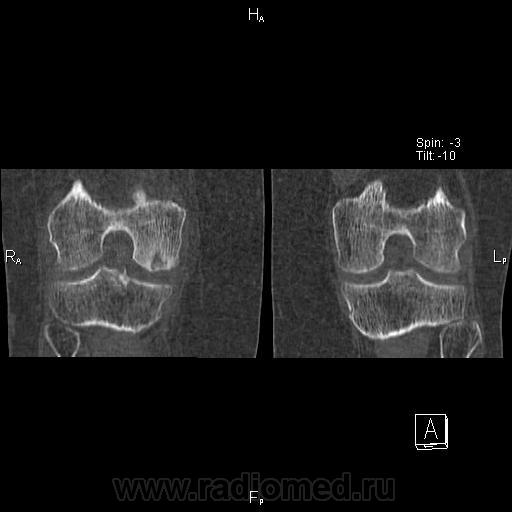

Здравствуйте! Давненько ничего не выкладывал. Нужна помощь. Женщина 1937 г.р. Жалобы на боли в правом коленном суставе уже давно. Долго ставили деф артроз.

Думаю что здесь частичный аваскулярный некроз медиального мыщелка бедренной кости. Ну а теперь вопросы:

3. Где выпот на КТ? Вижу в полости сустава и между мышцами по задней поверхности на уровне подколенной ямки( что это за сумка?). Забыл сделать реконструкцию с кернелем для мягких тканей, поэтому мягкие ткани такие пёстрые вышли, но выпот видно.

Да, но здесь часть эпифиза рассосалась, осталась только частично разрушенная субхондральная пластинка. Вот и думаю что это за стадия